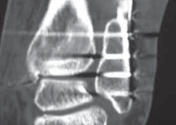

Malreduction of the ■ Bolster is placed under ankle, not foot. This will cause anterior displacement (

FIG 4B

). syndesmosis ■ A good lateral radiograph is obtained to assess reduction.

### FIG 4 • A. Identification and protection of the superficial peroneal nerve within the anterior flap. B. CT scan showing malreduction of the syndesmosis.